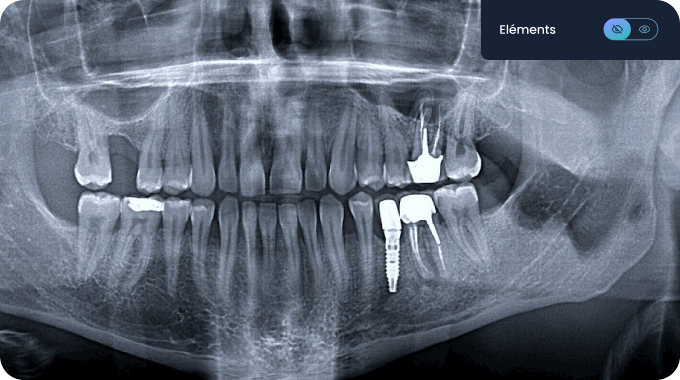

🔎 Allisone simplifie la lecture des radiographies pour les patients : grâce à des codes couleurs, chaque élément est mis en évidence sur la radiographie. Ainsi, les patients peuvent visualiser votre diagnostic et comprendre facilement les implications du plan de traitement proposé.

Analyse diagnostique par IA des radios dentaires

Identification des éléments pathologiques & non-pathologiques sur vos radios 2D.